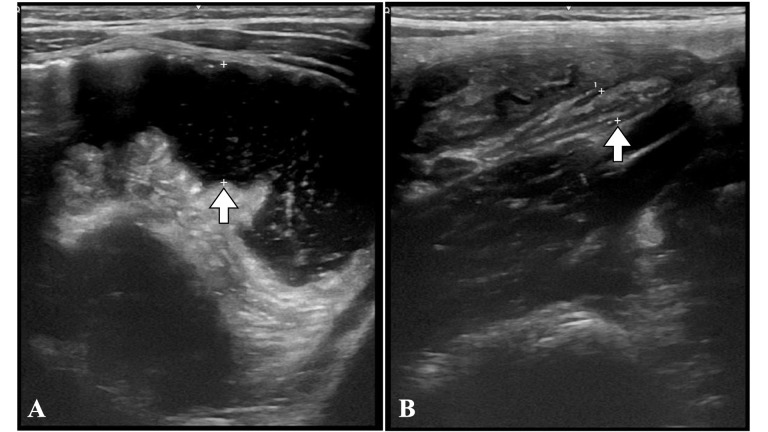

A 4-year-old male presented to the emergency department with fever, mucous diarrhea, abdominal pain, and vomiting for 36 hours. On abdominal palpation, he had generalized pain without rebound and increased hydroaereal sounds. The blood count showed leukocytosis and elevated C-reactive protein, and an ultrasound revealed intestinal loops with abundant content, increased peristalsis, and a normal appendix. Due to the suspicion of invasive gastroenteritis, he was admitted for observation. Due to the persistence of symptoms, a new ultrasound was performed which showed pelvic free fluid but did not identify the appendix. An abdominal radiography was previously performed, which showed an image compatible with appendicolith. With the suspicion of appendicitis, surgery was indicated, and an appendicular peritonitis was identified. The patient recovered well and was discharged seven days later. Diagnosing appendicitis in children can be a complex process. The most sensitive diagnostic tests are ultrasound and tomography. Abdominal radiography, however, is a widely available test with low radiation and has a positive predictive value of 90% for appendicitis (detecting appendicolith or periappendicular 'air silence'). In ambiguous cases, an abdominal X-ray could avoid invasive tests that require sedation or high doses of radiation.